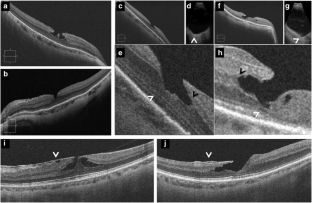

Fig. 2